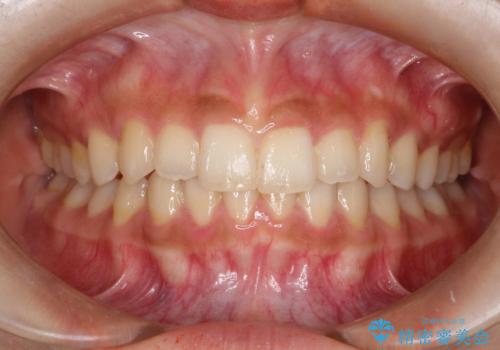

インビザラインを使用した深いかみ合わせの矯正

- 前歯のガタガタを主訴に来院された患者様です。

八重歯になっており、下顎の前歯が上顎の前歯に隠れてしまう、ディープバイトという状態でした。